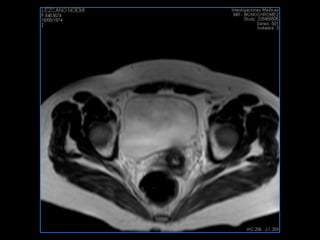

PROTOCOLO pelvis SAG T2, Y FAT SAT (FINOS) AXIAL T1  AX FAT SAT CON   GADOLINIO :  AX T1 Y COR T1 SAT: NO  FASE: RL THK: 3MM  COIL:  GAP: (FACTOR 1.4) 1MM FOV: 40 CM NEX:2 SINCRONIZACION RESPIRATORIA EN 3 O 4 CICLOS ALE